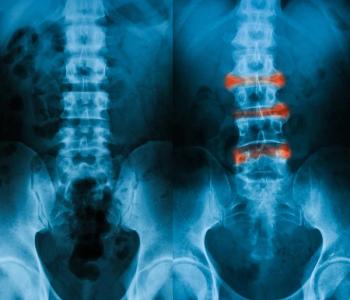

An expanded role for MRI and 2 recently approved treatment options.